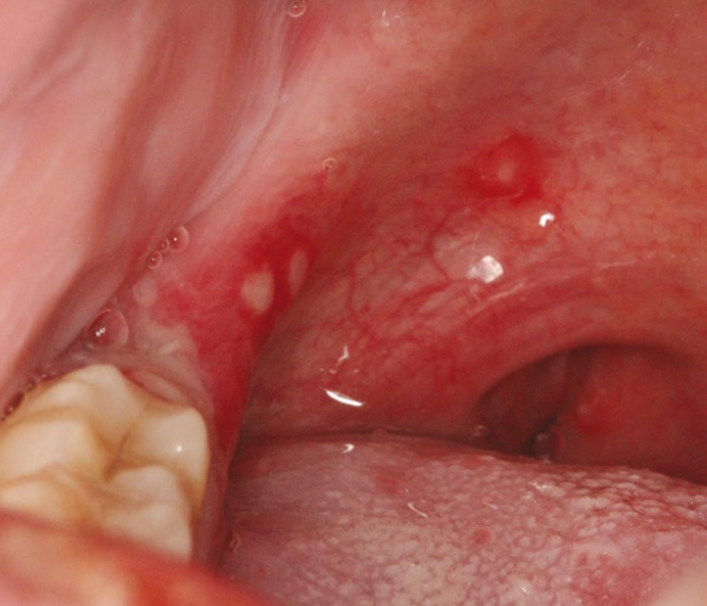

LİKEN PLANUS

Hastalığın kesin nedeni bilinmemekle birlikte, çevresel faktörler ve otoimmün bozukluklarla ilişkili olduğu düşünülen, ağız ve genital bölge başta olmak üzere vücudun çeşitli bölgelerini tutabilen enflamatuvar bir deri hastalığıdır. Kaşıntılı bir kızarıklığa sebep olur. 5p bulgusu. 1)pruritik 2)poligonal 3)purple 4)papül 5)parlak veya planar.

CloseLİKEN PLANUS

Hastalığın kesin nedeni bilinmemekle birlikte, çevresel faktörler ve otoimmün bozukluklarla ilişkili olduğu düşünülen, ağız ve genital bölge başta olmak üzere vücudun çeşitli bölgelerini tutabilen enflamatuvar bir deri hastalığıdır. Kaşıntılı bir kızarıklığa sebep olur. 5p bulgusu. 1)pruritik 2)poligonal 3)purple 4)papül 5)parlak veya planar.